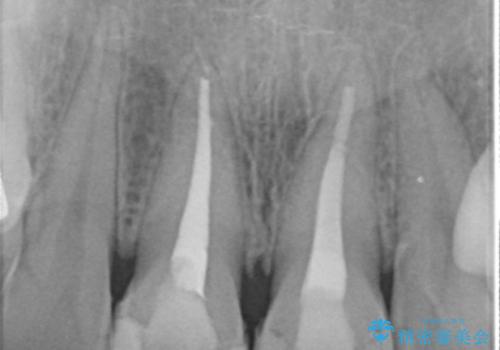

神経の方は問題なさそうだったため、患者様の希望でやりなおさず、土台とセラミック治療を行いました。

歯茎の黒ずみに関しては、中の歯の根が変色して透けている状態のため、変えることは難しいです。